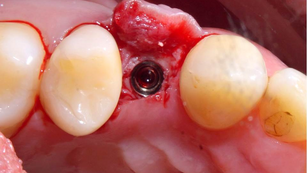

Immediate placement and loading with provisional screw retained crown at #21

Situation Patient Information Patient: 62 years old female Medical history: Hepa B, DM, HBP Chief complaint: "The upper front teeth are...

Dr. YoungKu Heo

Jan 8, 20162 min read